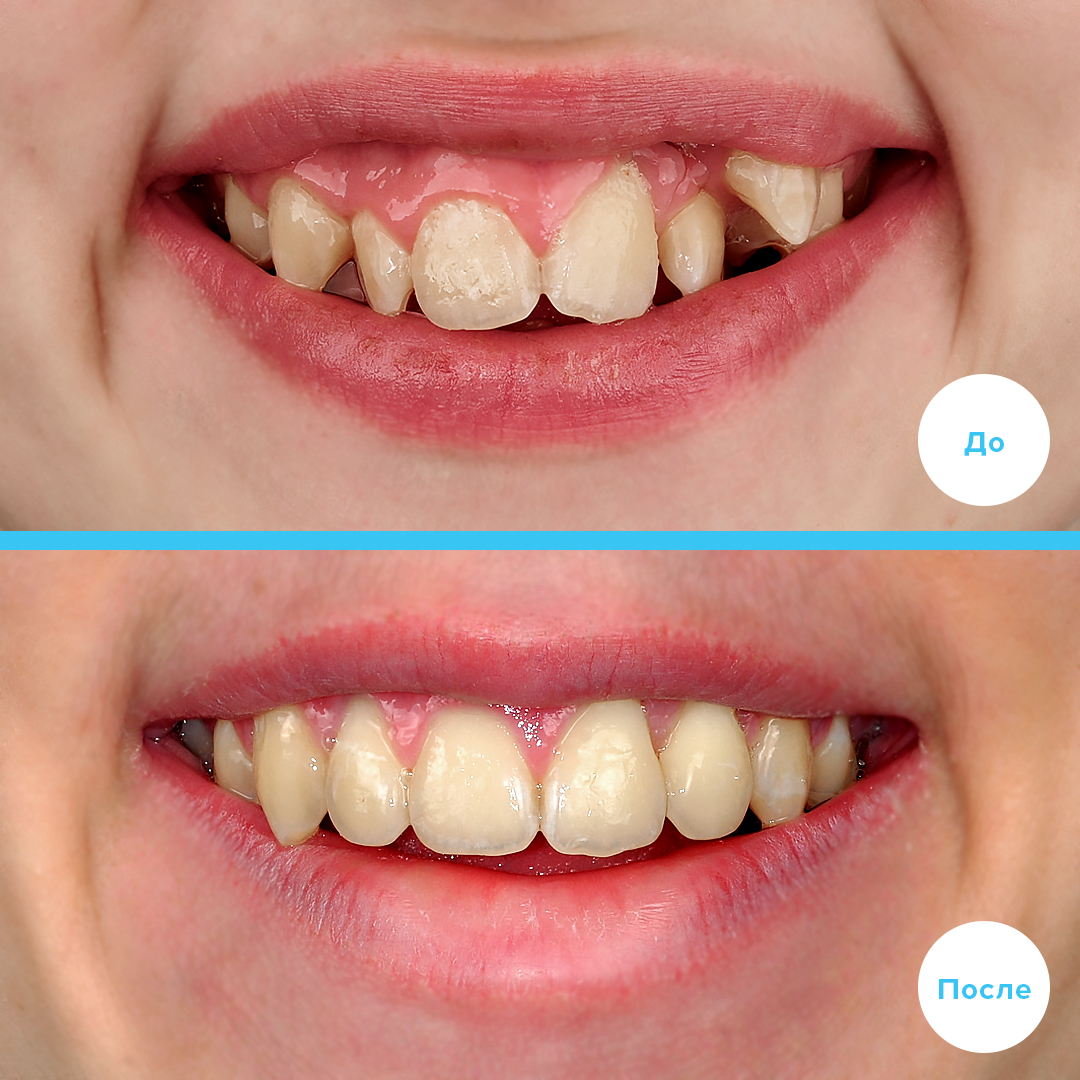

Коррекция скученности с удалением

Лечение скученности с удалением зубов и последующей установкой металлических самолигирующих брекетов Damon Q/Q

Пациенту 16 лет

Срок лечения: 2,5 года